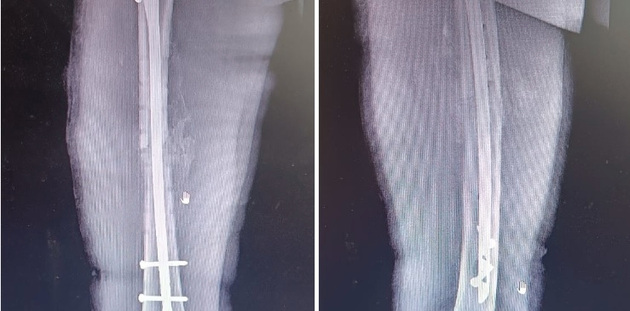

Фото: Муромская районная детская больница

Хирурги Муромской районной детской больницы внедрили лечение переломов трубчатых костей блокирующим интрамедуллярным остеосинтезом. Это инновационный метод, врачи получили лицензию на оказание высокотехнологичной медицинской помощи.

- Применение современного оборудования – электронно-оптического усиления изображения (С-дуги) – позволяет проводить операции с максимальной точностью и без рисков для здоровья, - рассказали в больнице.

Небольшая продолжительность операции, малая травматичность, малая инвазивность, возможность ранней безболезненной реабилитации, быстрое возвращение к привычному образу жизни, раннее восстановление трудоспособности - все это характеристики нового метода. На днях врачи Ойбек Косимов и Максим Смирнов успешно прооперировали им ребенка, попавшего в ДТП (мотоцикл столкнулся с легковушкой) и получившего серьезную травму - перелом бедра.